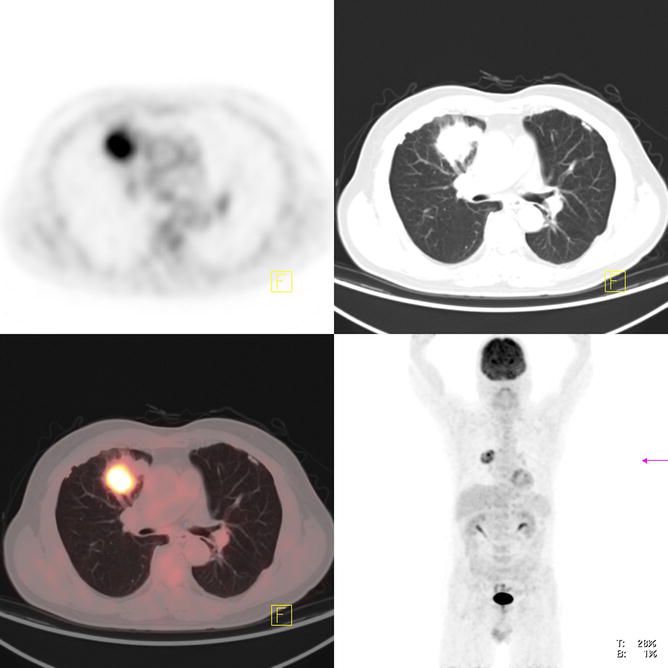

4. PET-CT的原理及其在肺癌治疗中的应用 PET-CT Principles and Applications in Lung Cancer Management By Long Chen, Hua Sun and Yunchao Huang

肺癌是世界上最常见的恶性肿瘤;正电子发射断层扫描(PET-CT)结合了来自PET的新陈代谢信息和来自CT的解剖学细节,这是目前最先进的技术。本文介绍了PET-CT及其在肺癌诊断、分期和治疗中的应用。从肺癌的临床特点、分型、分级、病理、PET-CT的原则、诊断和治疗的评价等方面进行了综述。详细说明了每种癌症亚型、分期标准和分类。内容将有利于临床医生以及放射科医生。